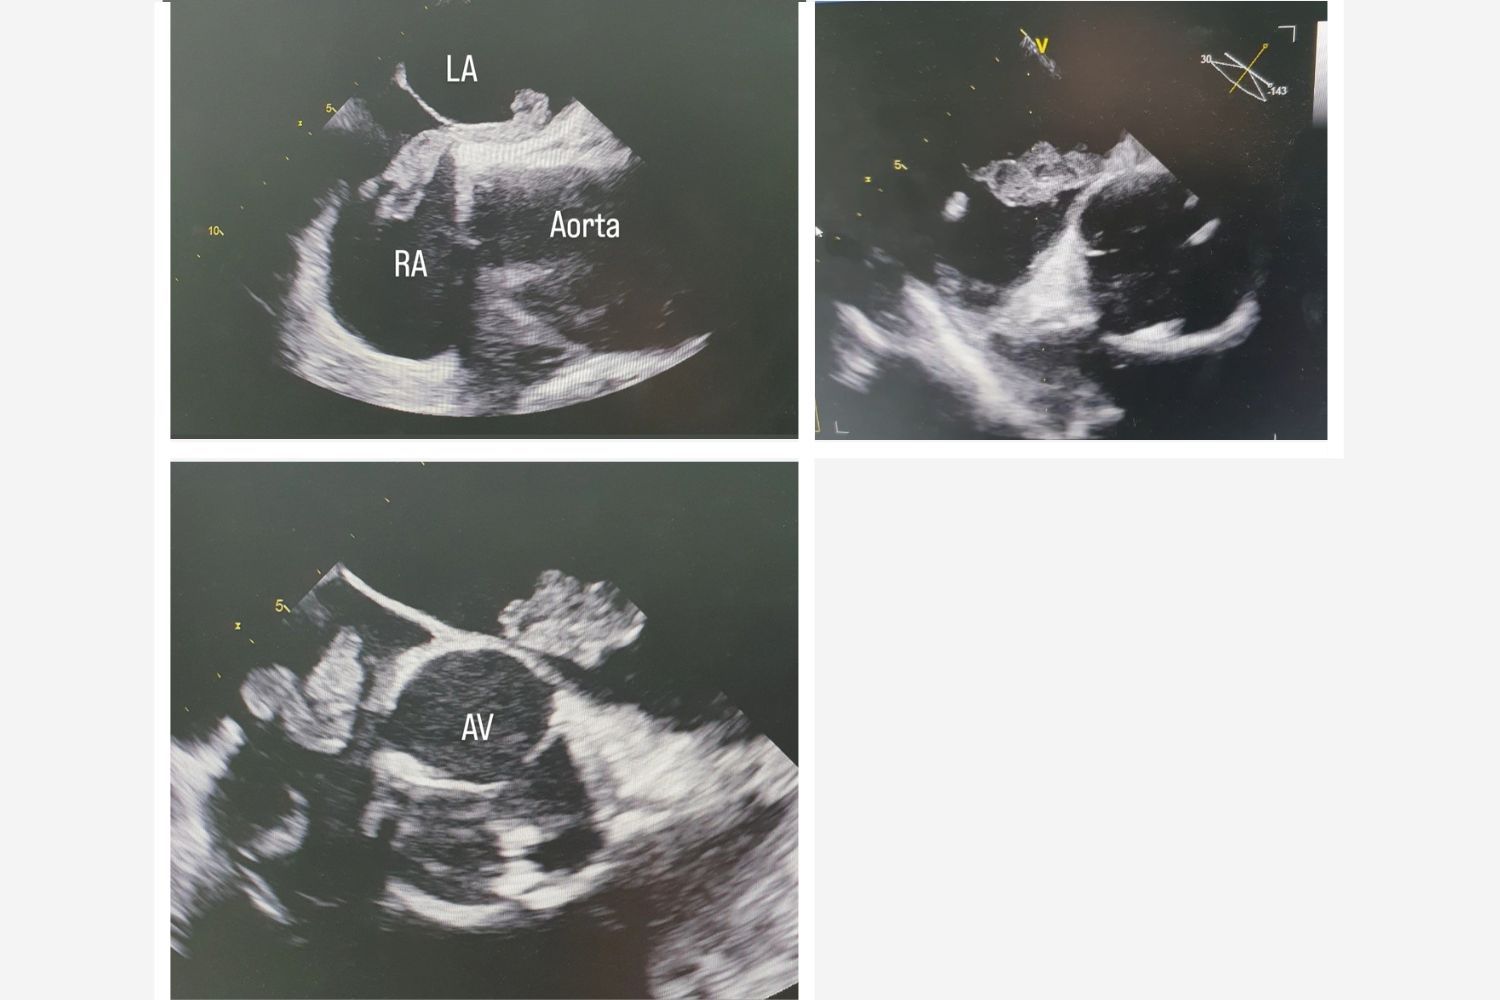

Image of the Week - 29 January 2025

28 January 2025

Image of the week